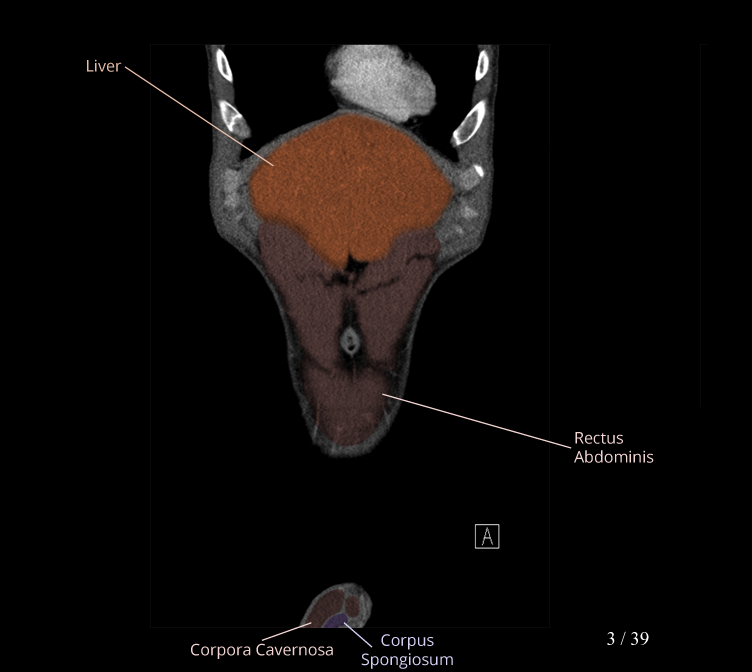

Body

Covers abdominal CT anatomy.